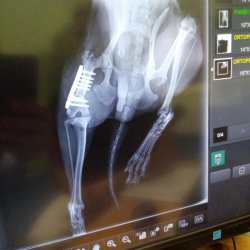

Quido se zlomenou stehenní kostí

Quido je maličký, 3,5 kg těžký psí hrdina, absolvoval operaci staré fraktury (zlomeniny) stehenní kosti, která byla velmi náročná. Trvala téměř 3 hodiny. Nakonec pan doktor opět poskládal nožku tak, jak má být, zlomenina se zpevnila pomocí úhlové stabilní ploténky s pěti šrouby a několika štěpů z holenní kosti. Quido si přes noc poležel na hospitalizaci a druhý den byl propuštěn do domácí péče, do dočasky, kde musí dodržovat přísný klidový režim. Nožičku je potřeba minimálně 1 - 2 týdny po operaci převazovat.